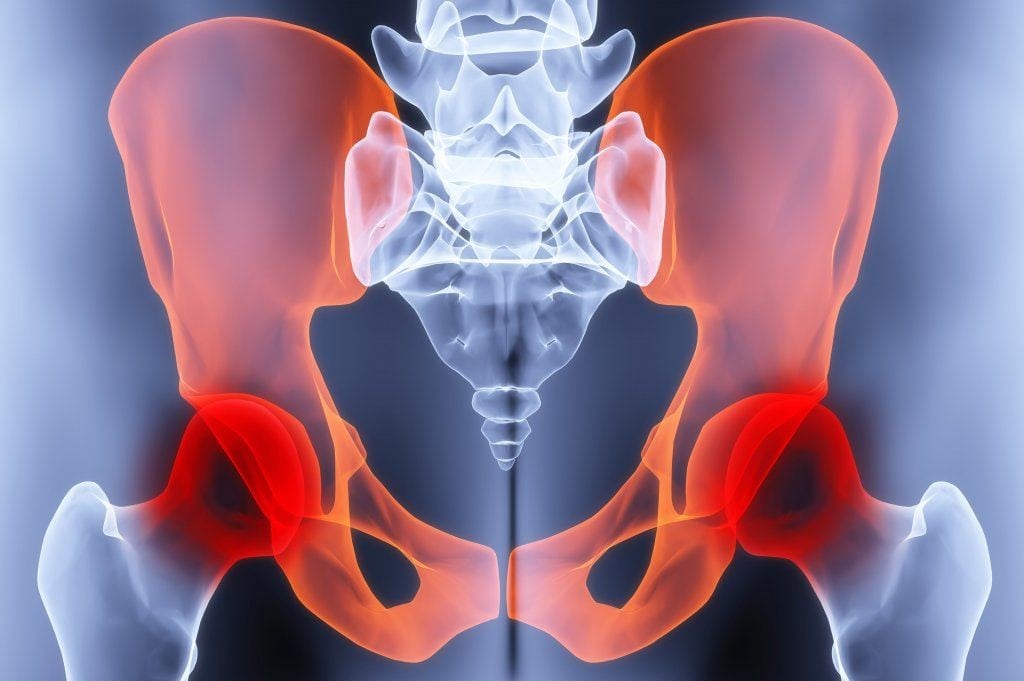

Остеохондроз поражает не только сегменты позвоночника — шейный, грудной, пояснично-крестцовый, но и крупные суставы. Самым большим в опорно-двигательном аппарате является тазобедренный, поэтому именно в нем начинают преждевременно разрушаться хрящи. Дегенеративно-дистрофическая патология манифестирует о себе острыми или тянущими, ноющими болями, отечностью, хрустом при ходьбе. При отсутствии врачебного вмешательства спустя несколько лет тазобедренный сустав частично или полностью утрачивает подвижность.

Остеохондроз ТБС развивается медленно, поэтому на начальном этапе человек не испытывает болезненные ощущения. Они появляются только через несколько месяцев. Боль не локализуется в самом тазобедренном суставе, а иррадиирует (распространяется) на поясницу, бедра, колени, пах. Движения становятся скованными, нередко больной сам намеренно ограничивает их, чтобы не испытывать боль. Тугоподвижность приводит к изменению походки, хромоте. Со временем атрофируются бедренные мышцы, и пораженная остеохондрозом нога укорачивается. Характерный признак патологии — ограниченное отведение нижней конечности. Например, больной не может сесть «верхом» на табурет.

На интенсивность всех симптомов остеохондроза тазобедренного сустава влияют степень поражения тканей, стадия течения патологии. Во время рецидивов человек страдает от острых, пронизывающих болей. Объем движений существенно ограничен. Часто больные в период обострения при ходьбе используют трость или костыли. А на последней стадии они не могут передвигаться без посторонней помощи.